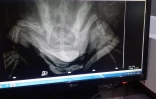

Une des tortues présente un enfoncement important de l’arrière de la carapace et une fracture ouverte de la nageoire arrière droite."Elle a été immédiatement emmenée chez le vétérinaire pour une radio et les premiers soins. La radio montre les traces d’un violent choc par l’arrière avec un enfoncement important de la carapace, une dévormation du bassin et du plastron et une fracture ouverte tibia-péroné" explique le centre de soin. Une seconde intervention est programmée jeudi matin pour réduire les fractures. La jeune tortue blessée est connue de Kelonia depuis 2015, grâce à la photo-identification.